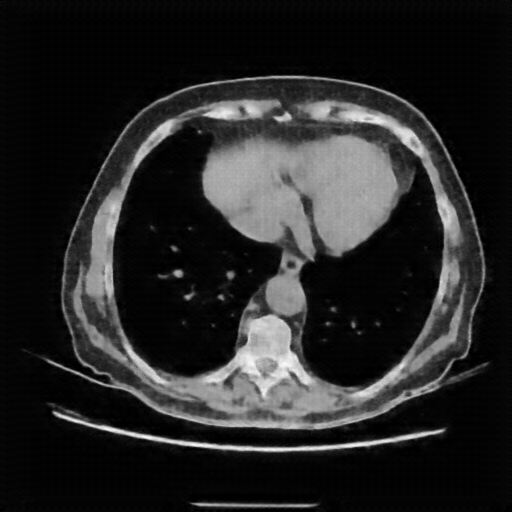

Generated VENOUS CT scan (A→B translation)

Full window (WL 1023.5, WW 4095 β†’ Low βˆ’1024, High +3071)

Lung window (WL -600, WW 1500 β†’ Low βˆ’1350, High +150)

Mediastinum window (WL 40, WW 400 β†’ Low βˆ’160, High +240)